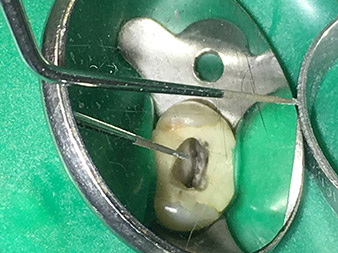

Dr. Nouraie: Ich bin sowohl mit der Abtragleistung als auch mit der Lebensdauer der Spitzen sehr zufrieden. Den runden Kopf der Spitze 4E würde ich noch runder gestalten. Bisher sind keine Spitzen während meines Gebrauchs frakturiert und ich konnte auch keine verminderte Abtragleistung selbst nach häufiger Verwendung feststellen. Besonders die beiden Spitzen 3E und 6E, die über eine zweite Abwinkelung verfügen, erleichtern den Einsatz im hinteren Molaren-Bereich bei Patienten mit eingeschränkter Mundöffnung enorm.

Dr. Nouraie: Die Ultraschall-Endodontie stellt für mich eine optimale Ergänzung zu den bisher verwendeten Techniken dar. Durch den Einsatz des erweiterten Endospitzen-Sortiments von W&H lässt sich die Qualität der Behandlung und somit die Langzeitprognose der Zähne deutlich verbessern. Die Spitzen zeichnen sich durch eine sehr hochwertige Verarbeitung aus und sind absolut empfehlenswert.

Besonders positiv sehe ich die Abtragleistung, die selbst nach häufigem Einsatz konstant bleibt, zudem gestaltet sich die Wiederaufbereitung der Instrumente sehr einfach und wirtschaftlich.